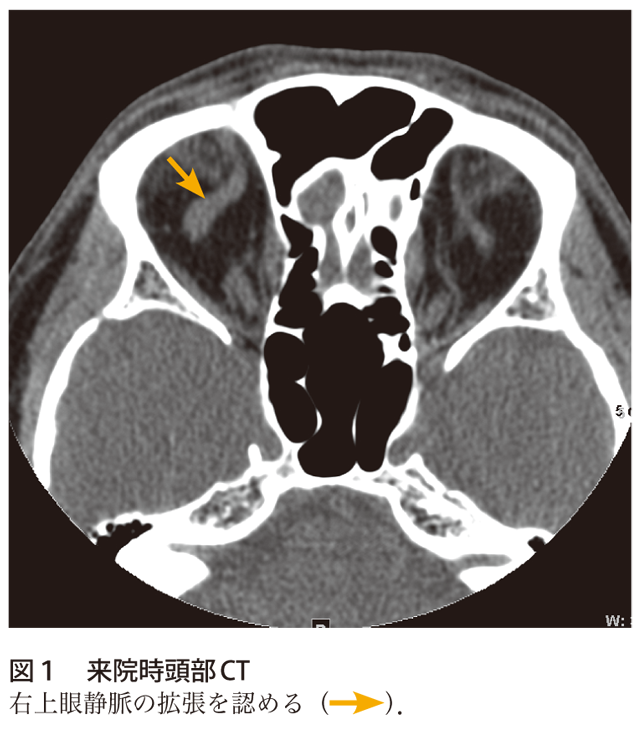

て,右内頸動脈海綿静脈洞瘻が疑われ同日緊急入院 となった。 初診時所見:意識清明で体温3 度であった。 視力は右05 左09 と右視力低下を認めた。右眼球 突出,右上眼瞼発赤・腫脹を認め(図1),開眼は 臨床 副鼻腔炎に続発した海綿静脈洞血栓症の1 例る深部の静脈洞血栓になりまして、こ の場合は意識障害が進行することもあ ります。 齊藤 視力障害などもあるのですか。 伊澤 海綿静脈洞血栓症の場合は目 の痛み、眼球突出、眼瞼浮腫、眼球運 動障害、このようなものも出てきます副鼻腔炎から海綿静脈洞血栓症,髄膜炎を併発し急激に失明に至った1症例 Loss of vision in a case of sinusitis with secondary cavernous sinus thrombosis and meningitis 小嶌 美恵子 1, 兜坂 法文 1, 和田 公平 2, 深尾 篤嗣 3 Mieko Kojima 1, Norifumi Tosaka 1, Kouhei Wada 2, Atsusi Fukao 3 1

右海綿静脈洞から蝶形頭頂静脈洞,一部眼窩にかけて高信号域を認めた. 表1 有痛性眼筋麻痺の原因疾患3)一部改変 血管障害 脳出血,くも膜下出血,下垂体卒中,脳動脈瘤,糖尿病性眼筋麻痺 (痛みは稀),ccf,海綿静脈洞血栓症化膿性海綿静脈洞血栓症,細菌性髄膜炎を来たしたLemierre症候群 52:7 Fig 1 Eye movement of the patient His right eye showed slight exophthalmos and swelling of the eyelid Lateral and inferior gaze of his right eye movement was disturbed Fig 2内科学 第10版 脳静脈洞血栓症・脳静脈血栓症の用語解説 概念 脳静脈洞が種々の原因による血栓で閉塞され頭痛などの脳圧亢進症状をきたすもので,血栓が静脈洞から脳表静脈に及ぶと脳局所症状を呈する.病変は脳静脈洞の血栓性閉塞が主体であるが,脳表静脈に血栓が進展した場合には